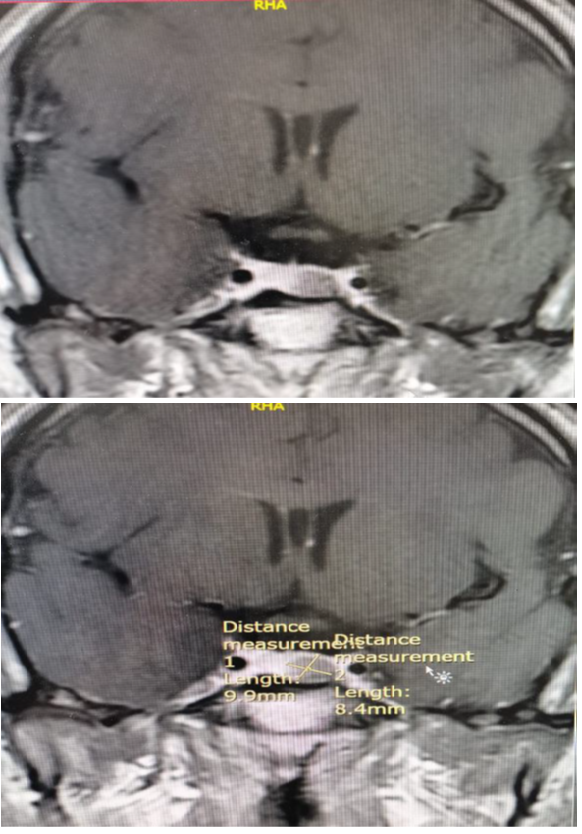

Our patient, Mr. X, a 34-year-old male, was referred to an endocrine clinic (in King Hussain Medical Center) to assess his thyroid status. Upon evaluation, he was anxious and irritated, and his sister said he had some behavioral changes for the last few months. He was usually calm and friendly, she said he lost weight despite his increased appetite. His past medical history was significant for epilepsy and minor cardiac anomalies (atrial septal defect and atrioventricular canal). During examination, he had a small firm goiter with no bruit or thrill on palpation. He also had tremors of outstretched extremities, but no opthalmopathy which can be related to thyroid disorders, galactorrhea, or acromogelic features. His heart rate was 105, and his blood pressure was 127/80. His laboratory investigations showed a thyroid function test (tft) with elevated TSH level 17 (normal range: 0.34–5.6 μU/L) and elevated free thyroxine level 2.46 (normal range: 0.7-1.8 ng/dl). We ran the test again, and it revealed similar readings. Previous thyroid function tests were normal, so a thyrotoxic condition was considered. A beta-blocker was prescribed to the patient, and it had a dramatic effect on controlling his symptoms. Ultrasonography showed a mild goiter with hypervascularity, and the thyroid scintigraphy scan showed thyroid enlargement with hypervascularity (Figure 1), so a diagnosis of hyperthyroidism was confirmed. An auto-antibody panel was sent, and it came back negative. The sex hormone binding protein was a high normal 51.97 nmol/l (range 18.3–54.1), the alpha subunit wasn't done due to unavailability. Growth hormone and prolactin were normal. In addition, pituitary magnetic resonance imaging (MRI) (Figure 2), (Figure 3), (Figure 4) was done, and it showed a microadenoma of 9.9*8.4 mm dimensions with no pressure effect on the pituitary stalk and optic chiasm. He underwent visual perimetry and his visual fields were normal. As we suspected a TSH-secreting pituitary tumor, a somatoastain analogue was given to the patient for both diagnostic and therapeutic purposes.4–7 Tsh level showed significant suppression (15 to 5 normal range: 0.34–5.6 μU/L), four weeks following the somatostatin analogue injection. As surgery is the first-line treatment for Tsh-oma, his case was discussed with the neurosurgeons, and the patient was sent for surgery. Before surgery, his heart rate was controlled by beta blockers, and then he underwent transsphenoidal surgery by an expert neurosurgeon with no significant postoperative complications.8

Figure 2 Coronal pituitary MRI.

Figure 3 Technitium scan of the thyroid.